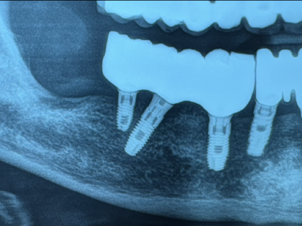

"Rigenerazione ossea guidata (GBR) in sede crestale mediante innesto osseo con biomateriale osteoconduttivo, ricoperto da membrana di collagene , in associazione a impianti dentali endossei. La procedura favorisce l’osteointegrazione degli impianti e la neoformazione di tessuto osseo alveolare."